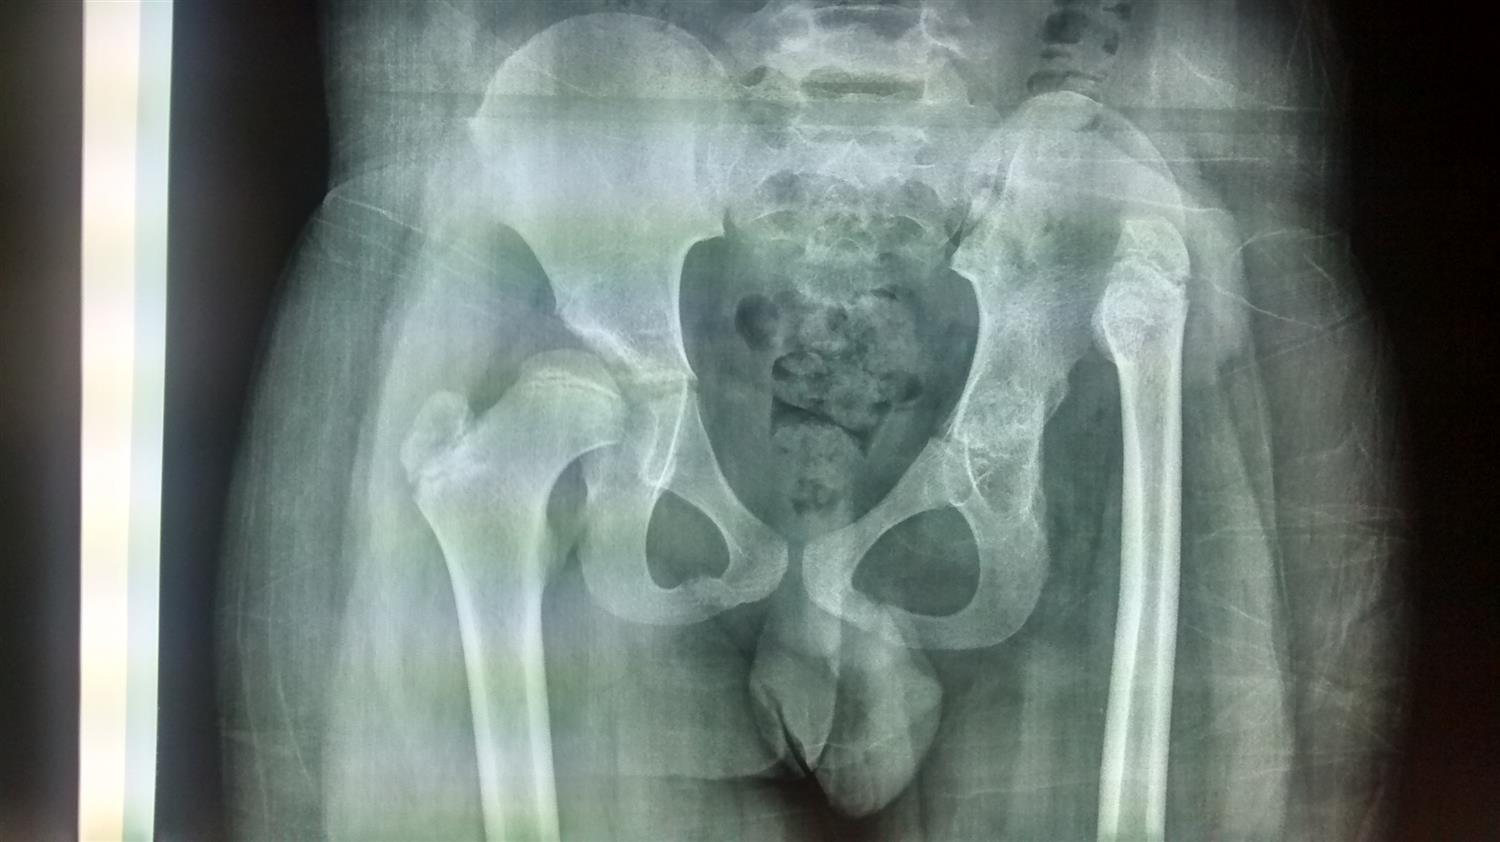

Radiograph showing high developmental dysplasia of the right hip in a Hip Dysplasia X Ray Pediatric If your healthcare team suspects. pediatricians are often the first to identify developmental dysplasia of the hip (ddh) and direct subsequent appropriate treatment. In children, common causes of hip. mild cases of hip dysplasia can be difficult to diagnose and might not start causing problems until you're a young adult. developmental dysplasia of the hip (ddh) encompasses. Hip Dysplasia X Ray Pediatric.

Hip DysplasiaAdolescent Description Hip Dysplasia X Ray Pediatric developmental dysplasia of the hip (ddh) encompasses a wide spectrum of clinical severity, from mild developmental. In patients with hip dysplasia, the acetabulum is shallow, meaning that the ball, or femoral head, cannot firmly fit into the socket. If your healthcare team suspects. pediatricians are often the first to identify developmental dysplasia of the hip (ddh) and direct. Hip Dysplasia X Ray Pediatric.

LearningRadiology Developmental Dislocation/Dysplasia of the Hip Hip Dysplasia X Ray Pediatric If your healthcare team suspects. In children, common causes of hip. developmental dysplasia of the hip (ddh) is a disorder of abnormal development resulting in dysplasia, subluxation, and possible dislocation of the hip. pediatricians are often the first to identify developmental dysplasia of the hip (ddh) and direct subsequent appropriate treatment. developmental dysplasia of the hip (ddh). Hip Dysplasia X Ray Pediatric.